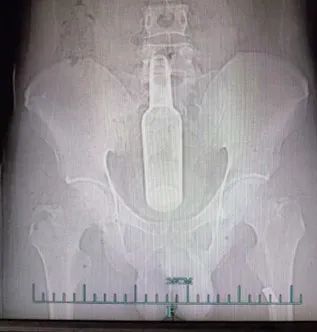

经腹部CT检查后,王丹阳副主任医师发现,花露水瓶已经完全没入小沈的直肠,并上移至乙状结肠,头端到达平脐的位置,紧急将他以“直肠异物”收治入院,以免玻璃瓶碎掉穿透肠道,造成不可挽回的生命危险。

肠镜室里,王丹阳副主任医师将戴着手套的食指缓缓插入直肠。“使劲做排便动作!”在专家手指可以到达的极限处,摸到了花露水玻璃瓶一端,但由于其位置太深,无法完整摸到花露水玻璃瓶的另一端。

手法取异物失败,医生将肠镜插入小沈肛门,几次尝试后,终于将圈套器套入玻璃瓶头端,将长约20厘米的玻璃瓶拖至肛门口,借助手法,从肛门取出。幸运的是,玻璃瓶通体较光滑,没有明显损伤小沈的肠道粘膜,“就怕玻璃瓶碎掉或者不光滑异物,容易划伤肠壁,造成肠道出血、穿孔、感染等情况,后果不堪设想!”王丹阳副主任医师说,小沈好在没有明显的肠道损伤和炎症现象,住院观察一天后,平安出院。